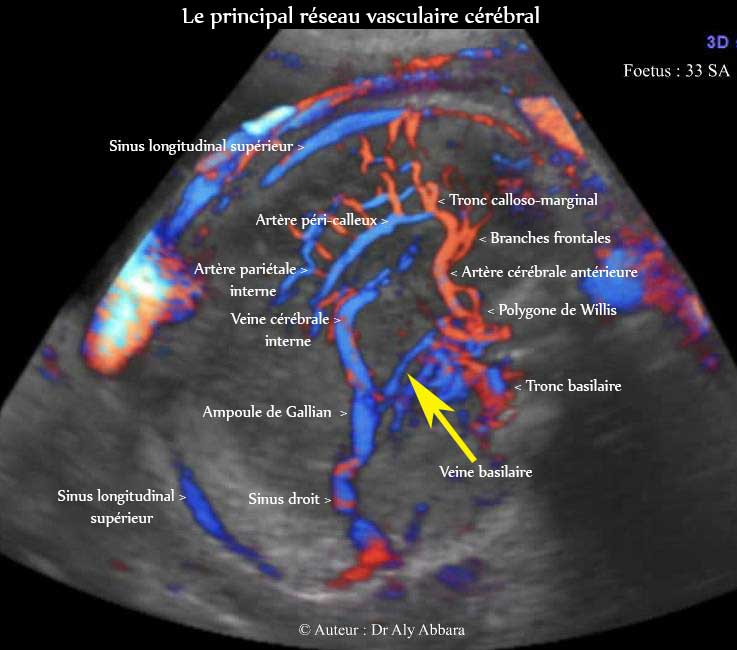

Images échographiques montrant le réseau vasculaire artério-veineux principal du cerveau fœtal

Fœtus âgé de 33 SA

Auteur : Dr Aly Abbara